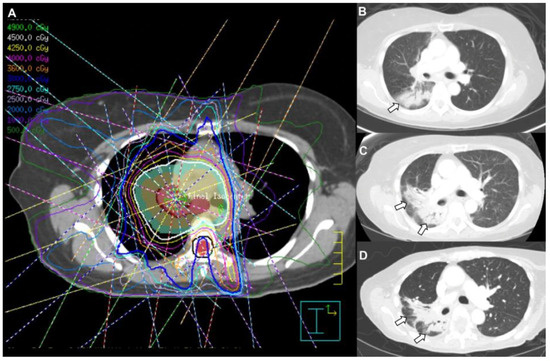

Pulmonary Complications of Cancer Therapy: Clinical Presentations, Imaging Patterns, and Management Strategies

by Bilal Zafar, Tasmea Haque, Miranda Tan, Ritika Singh, Lara Bashoura, Ajay Sheshadri, Maria Azhar and Saadia A. Faiz

Background and objectives: Therapeutic agents for cancer can cause unique pulmonary toxicities and mimic other conditions. The advent of new targeted molecular and immune therapies has changed the landscape of cancer treatment. These adverse events pose diagnostic and therapeutic challenges. This review aims to summarize the clinical presentations, radiographic patterns, and management strategies for noninfectious pulmonary complications associated with cancer therapies. Materials and methods: A literature review was conducted focusing on drug-induced lung injury (DILI), radiation-induced lung injury (RILI), pleural disease, pulmonary vascular complications, and other inflammatory conditions in patients with cancer. The data sources included clinical trials, guideline recommendations, observational studies, and expert consensus addressing incidence, pathophysiology, imaging findings, and treatment approaches. Results: Noninfectious pulmonary sequelae of anti-neoplastic therapies encompass a broad spectrum of etiologies. DILI occurs in up to 30% with variable onset and severity. The patterns can be diverse but include interstitial pneumonitis, organizing pneumonia, and diffuse alveolar damage. RILI is common and influenced by the radiation dose, volume, and concurrent therapies, and it may have both acute and chronic clinical and radiographic presentations. Pleural disease may arise from radiation and other agents, and the determination of etiology can impact management. Pulmonary vascular disease arises from many different etiologies, including therapies such as tyrosine kinase inhibitors and proteosome inhibitors, thromboembolic disease, as well as rare processes, including pulmonary veno-occlusive disease. Other conditions such as transfusion-related lung injury, cryptogenic organizing pneumonia, and interstitial lung abnormalities can also further complicate the diagnosis. Conclusions: Noninfectious pulmonary complications related to cancer therapies are diverse and often indistinguishable from infectious or malignant processes. The integration of clinical history, imaging, and selective invasive testing are needed for a timely diagnosis. Management typically involves withdrawal of the offending agent and corticosteroids, with immunosuppressive therapy reserved for severe or refractory cases. The awareness of these entities and early recognition are critical to optimizing outcomes. Full article

(This article belongs to the Section Pulmonology)